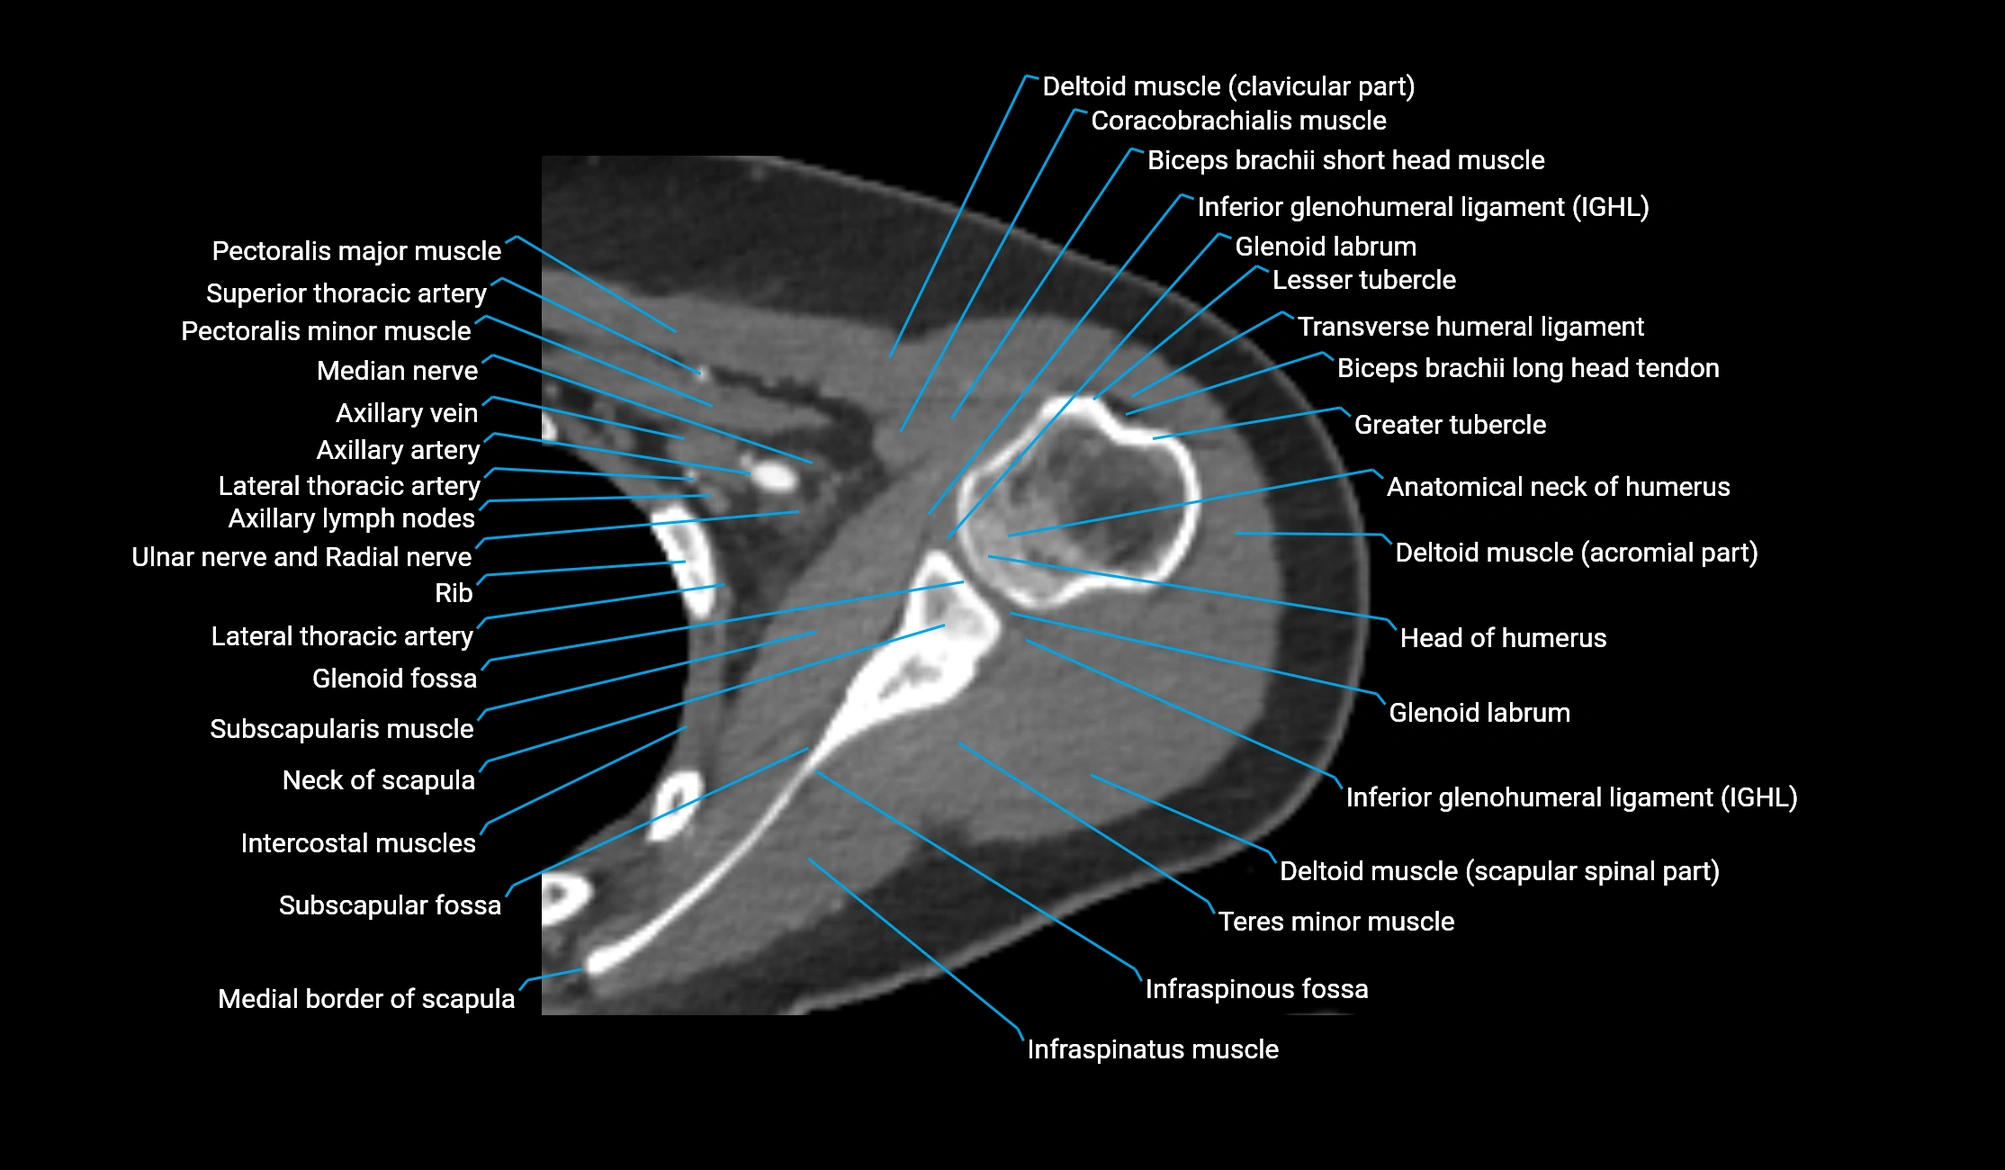

CT image